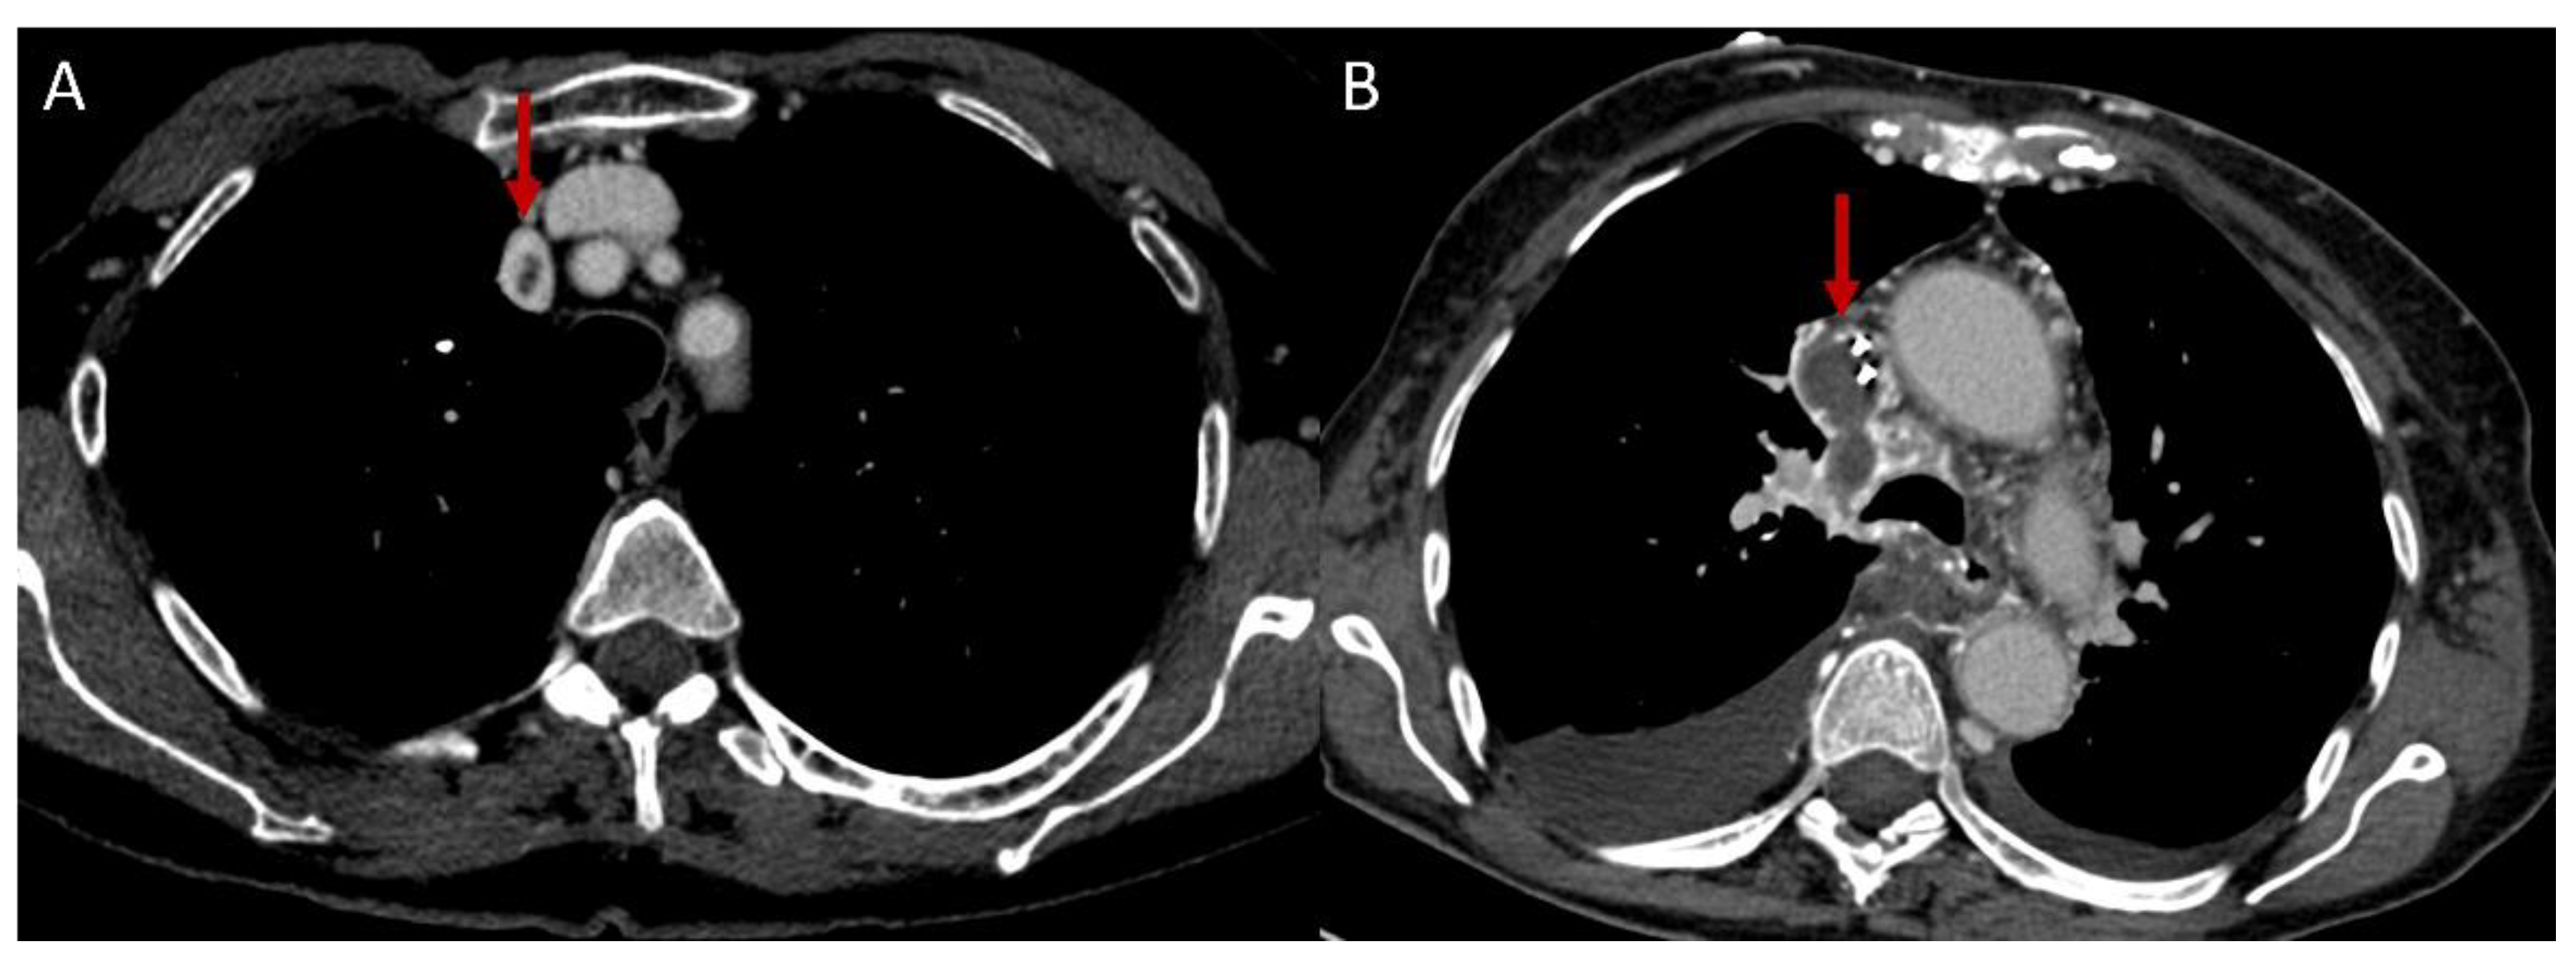

- Chae, E.J.; Do, K.H.; Seo, J.B.; Park, S.H.; Kang, J.W.; Jang, Y.M.; Lee, J.S.; Song, J.W.; Song, K.S.; Lee, J.H.; et al. Radiologic and Clinical Findings of Behçet Disease: Comprehensive Review of Multisystemic Involvement. Radiographics 2008, 28, 1–56. [Google Scholar] [CrossRef]

- Ceylan, N.; Bayraktaroglu, S.; Erturk, S.M.; Savas, R.; Alper, H. Pulmonary and Vascular Manifestations of Behcet Disease: Imaging Findings. AJR Am. J. Roentgenol. 2010, 194, W158–W164. [Google Scholar] [CrossRef]